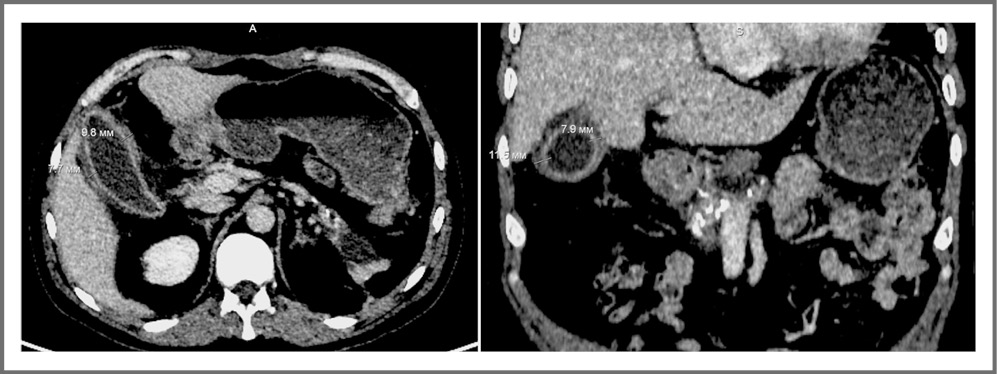

Выполнена СКТ живота (рис. 5), пациент осмотрен хирургом, диагностирован ОНХ. Больной переведен в профильную хирургическую клинику, где выполнена лапароскопическая холецистэктомия (рис. 6). Эндоскопическая картина представлена ЖП, увеличенным в размере (10×5×3 см), стенка пузыря отечна, инъецирована сосудами, обложена фибрином в области дна и тела. В послеоперационном периоде отмечалось уменьшение болей в правом подреберье, исчезновение тошноты, однако сохранялась фебрильная лихорадка до 39,0°С. В клиническом анализе крови обращал на себя внимание нейтрофильный лейкоцитоз до 24,1×109/л без палочкоядерного сдвига, лимфопения, тромбоцитоз до 596×109/л, эритропения до 3,40×1012/л, повышение скорости оседания эритроцитов до 55 мм/ч. В биохимическом анализе крови аланинаминотрансфераза, аспартатаминотрансфераза, билирубин в пределах нормы, отмечались гипопротеинемия до 55,2 г/л, гипергликемия до 12 ммоль/л, повышение СРБ до 163,51 мг/л.

Рис. 5. СКТ живота от 09.11.2021. ЖП увеличен до 100×43 мм. Отмечается утолщение стенки ЖП до 11,5 мм и ее локальное расслоение на уровне дна. В просвете прослеживается жидкостное содержимое. Окружающая клетчатка реактивно уплотнена.

Fig. 5. CT scan of the abdomen from 11.09.2021. The gallbladder is enlarged to 100×43 mm. There is a thickening of the gallbladder wall up to 11.5 mm and its local stratification at the level of the bottom. Fluid content is visible in the lumen. Surrounding tissues are reactively changed.